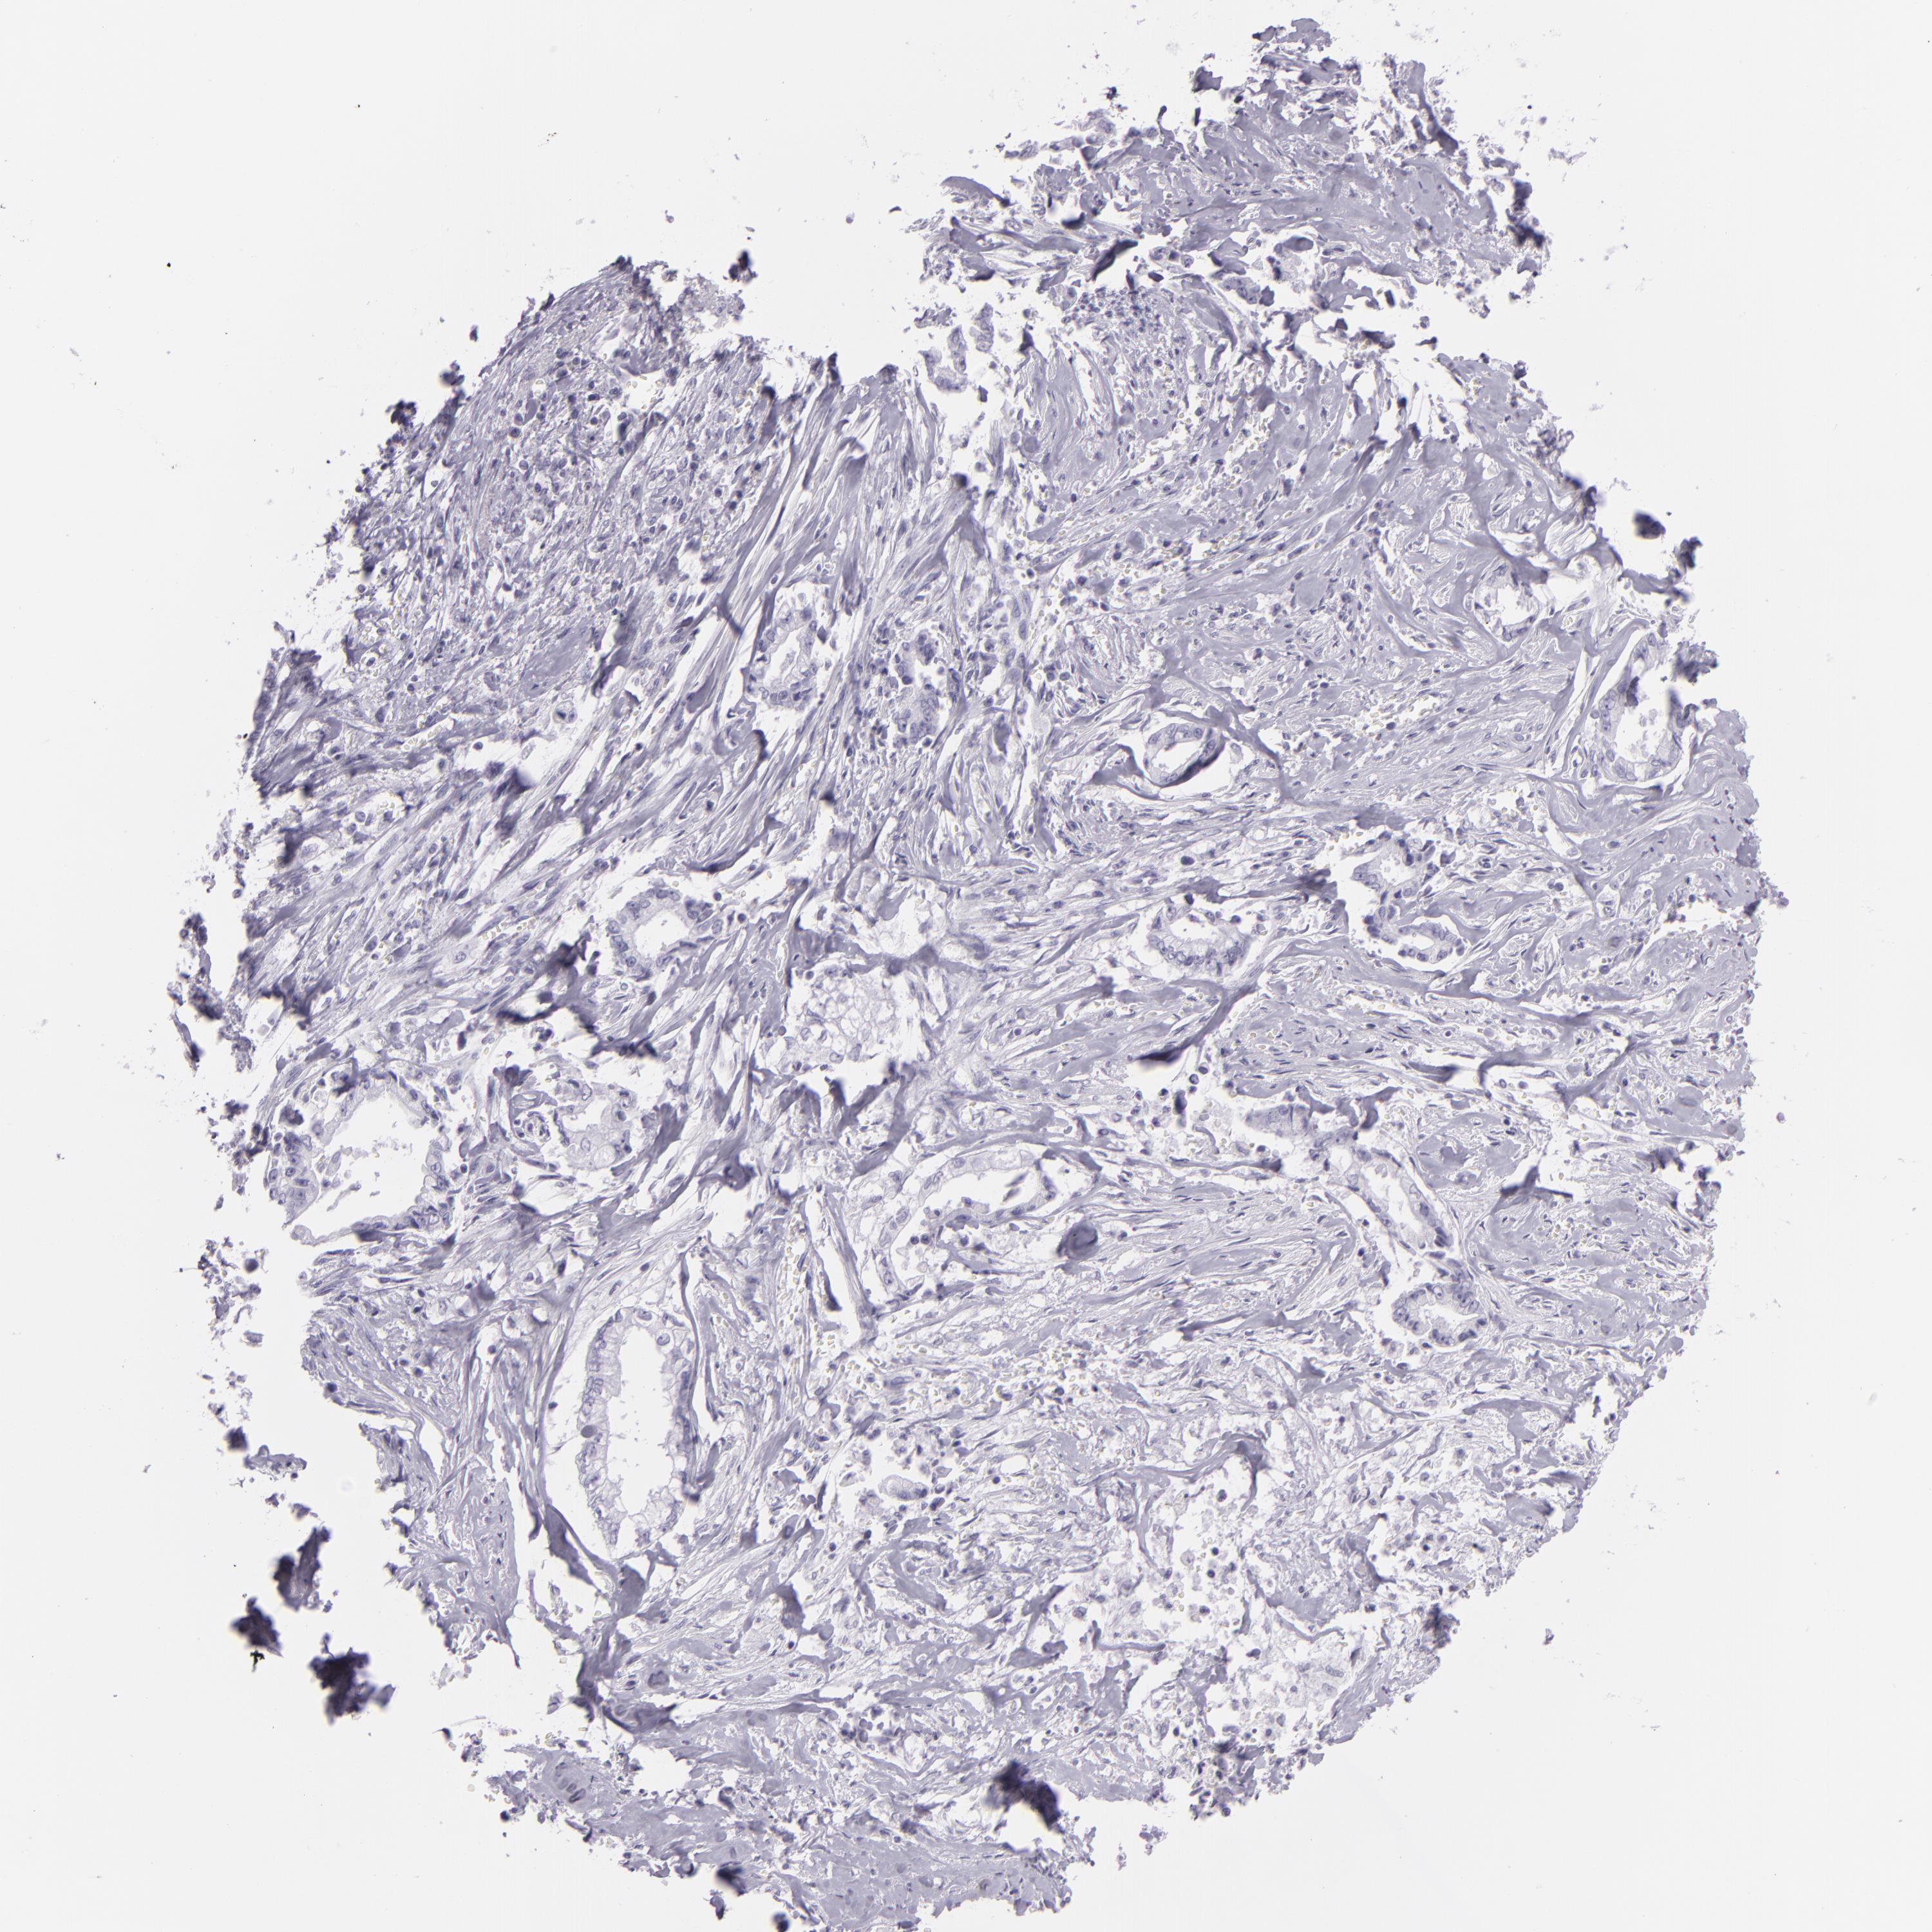

LIVER CANCER - Protein expressioni

A mouse-over function shows sample information and annotation data. Click on an image to view it in a full screen mode. Samples can be filtered based on level of antibody staining by selecting one or several of the following categories: high, medium, low and not detected. The assay and annotation is described here.

Note that samples used for immunohistochemistry by the Human Protein Atlas do not correspond to samples in the TCGA dataset.

Antibody stainingi

Antibody staining in the annotated cell types in the current human tissue is reported as not detected, low, medium, or high, based on conventional immunohistochemistry profiling in selected tissues. This score is based on the combination of the staining intensity and fraction of stained cells.

Each image is clickable and will lead to virtual microscopy that enables deeper exploration of all samples and also displays staining intensity scores, fraction scores and subcellular localization as well as patient and tissue information for each sample.

Antibody CAB002165

Staining

High

Medium

Low

Not detected

Intensity

Strong

Moderate

Weak

Negative

Quantity

>75%

75%-25%

<25%

None

Location

Nuclear

Cytoplasmic/membranous

Cytoplasmic/membranous,nuclear

Carcinoma, Hepatocellular, NOS

Cholangiocarcinoma